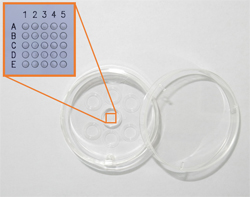

Embryo Culture Dish

With the droplet culture method that is the general cultivation method in use, group culture that cultivates multiple embryos in a drop culture medium in order to promote embryo development is cited as desirable. With currently available dishes, however, this has not been possible.

The dedicated dish used in the new system has been designed to provide the optimal culture environment for embryos. It is easy to individually manage embryos via multiple micro-wells, which also allow for the establishment of group culture.